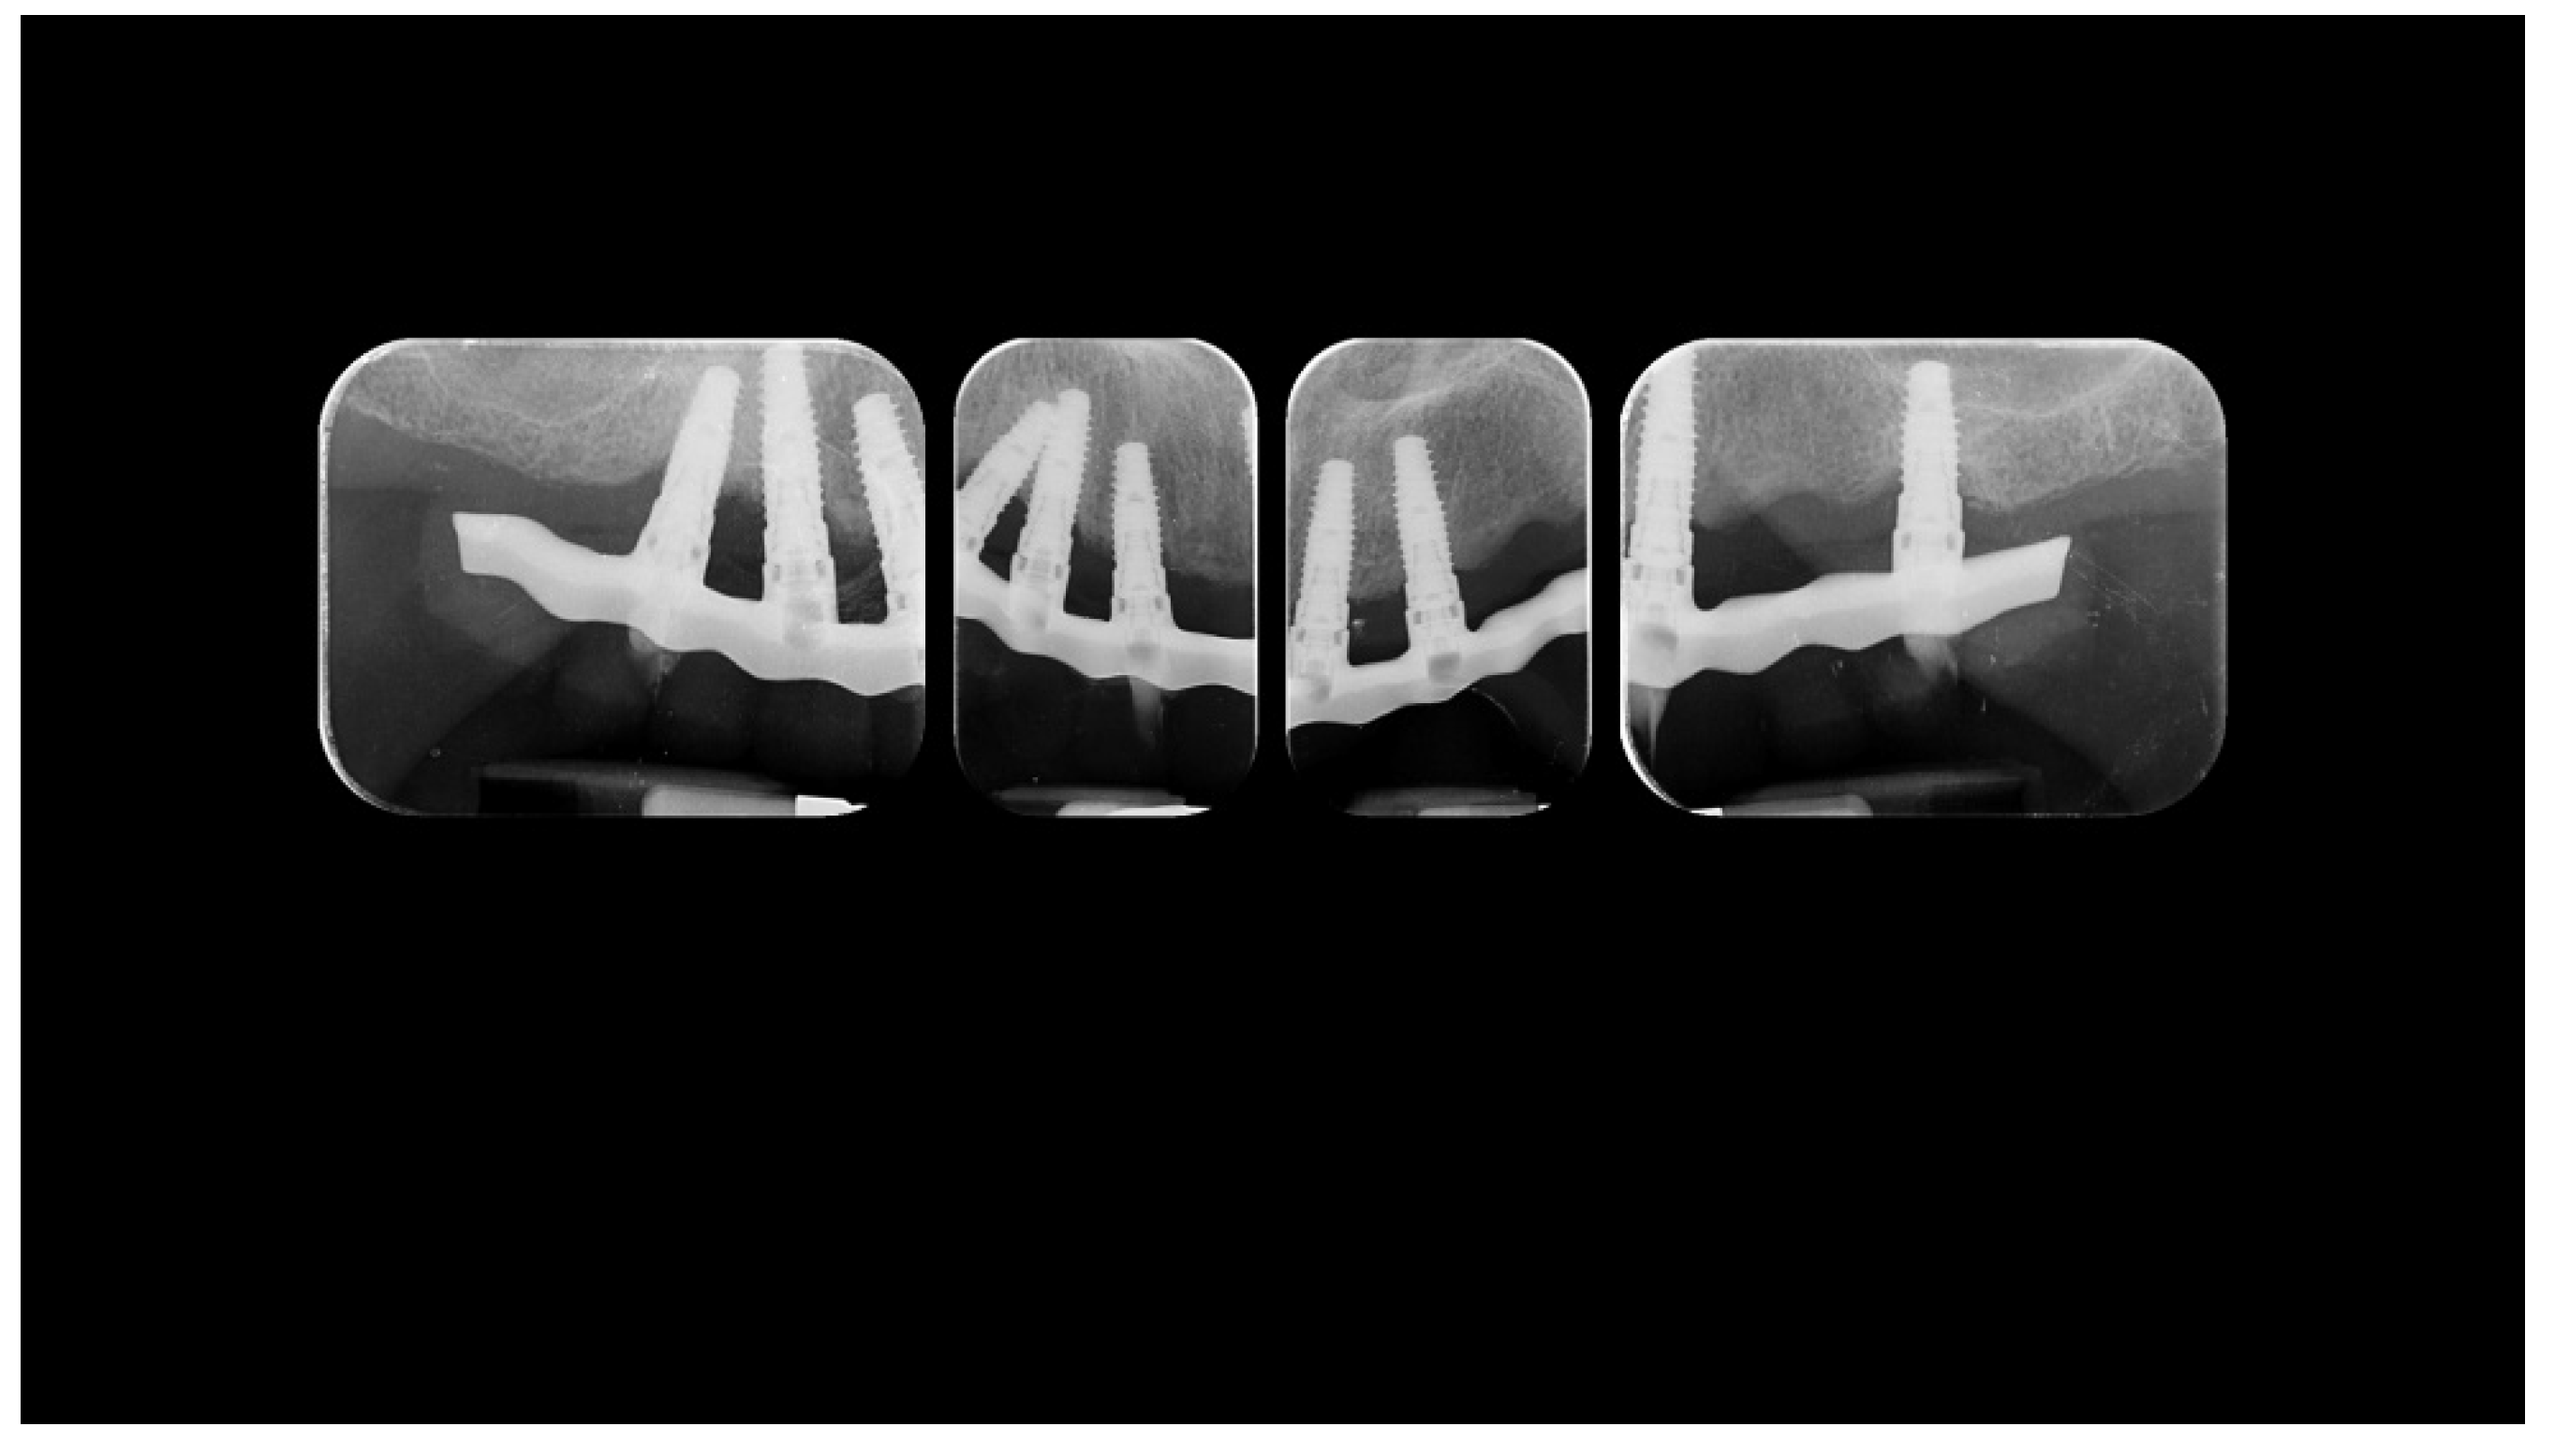

Figure 4.

Radiographic status of the previous restoration.